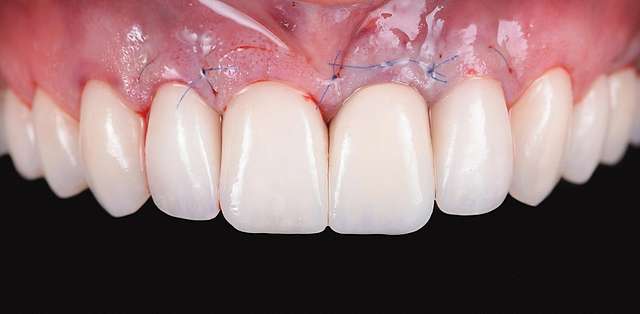

A gingival graft is a micro-surgery that will transplant a bulk of soft tissue - free gingiva or connective tissue ( the internal layer of gingiva ) to cover a soft tissue defect. Usually this type of procedures is required to augment implants, or to cover defects caused by periodontal disease or trauma. The grafts are harvested from the third molar region or the palate, and are transported where they are needed.

This type of procedure is a very delicate one, using the same type of blades like the ones used in ophthalmology and the sutures are also very thin. The sutures will be removed after 7-14 days, depending on the case, when primary healing is achieved. The maturation of the graft will take roughly 90 days, this is the reason why, when placing implants we prefer to also do the graft, so we can sync the healing time for both procedures.

Using tissue grafts to correct gingival levels or cover recessions